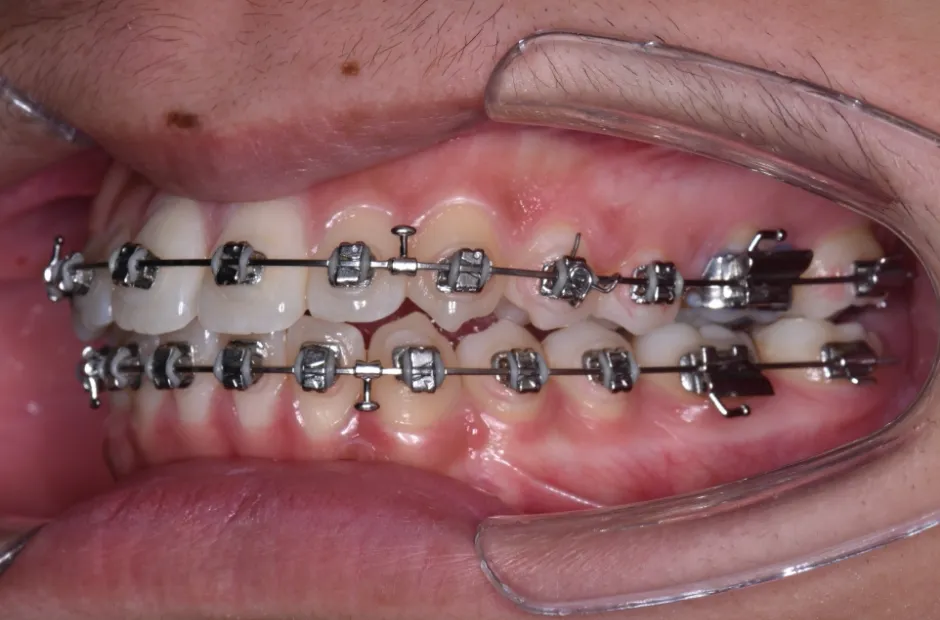

| 診断名・主訴 | 下顎前突、叢生 |

|---|---|

| 年齢・性別 | 23歳・女性 |

| 治療期間・回数 | 3年 |

| 治療に用いた主な装置 | 上顎5,5 下顎4,4 |

| 抜歯部位 | 舌側矯正 |

| 治療費 | 100万円(税抜) |

| リスク・副作用 | 装置による違和感・疼痛・歯肉退縮・歯根吸収・虫歯のリスクなど |

治療中